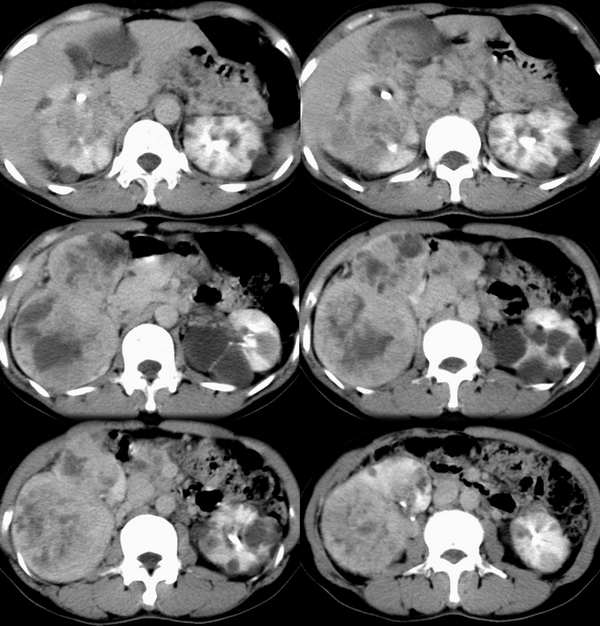

女性, 40岁。 10年前曾因腰痛在外院诊断双侧多囊肾并右肾多发结石(有静脉肾盂造影及b超报告,但没能见到影像图片)并行碎石处理且有排石史,后来一直无明显异常。但近2个月来自觉肝区饱满、右侧膈肌上抬,并进行性加重;血尿常规及淀粉酶阴性,血压正常。

平扫

右肾体积增大,形态失常,其内可见多发低密度影,增强后动脉期病灶实质明显强化,低密度区未见强化,静脉期病灶呈等密度,考虑右肾癌,左肾多发囊肿,多囊胰

右肾体积增大,形态失常,其内可见多发低密度影,增强后动脉期病灶实质明显强化,低密度区未见强化,静脉期病灶呈等密度.